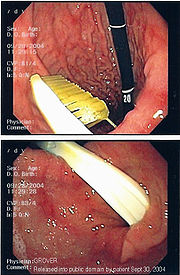

Commonly swallowed objects include coins, buttons, batteries, and small bones (such as fish bones), but can include more complex objects, such as eyeglasses, spoons, and toothbrushes (see image).

Endoscopic retrieval involves the use of a gastroscope or an optic fibre charge-coupled device camera. This instrument is shaped as a long tube, which is inserted through the mouth into the esophagus and stomach to identify the foreign body or bodies. This procedure is typically performed under conscious sedation. Many techniques have been described to remove foreign bodies from the stomach and esophagus. Usually the esophagus is protected with an overtube (a plastic tube of varying length), through which the gastroscope and retrieved objects are passed.

Once the foreign body has been identified with the gastroscope, various devices can be passed through the gastroscope to grasp or manipulate the foreign body. Devices used include forceps, which come in varying shapes, sizes and grips, snares, and oval loops that can be retracted from outside the gastroscope to lasso objects, as well as Roth baskets (mesh nets that can be closed to trap small objects), and magnets placed at the end of the scope or at the end of orogastric tubes. Some techniques have been described that use foley catheters to trap objects, or use two snares to orient foreign bodies.